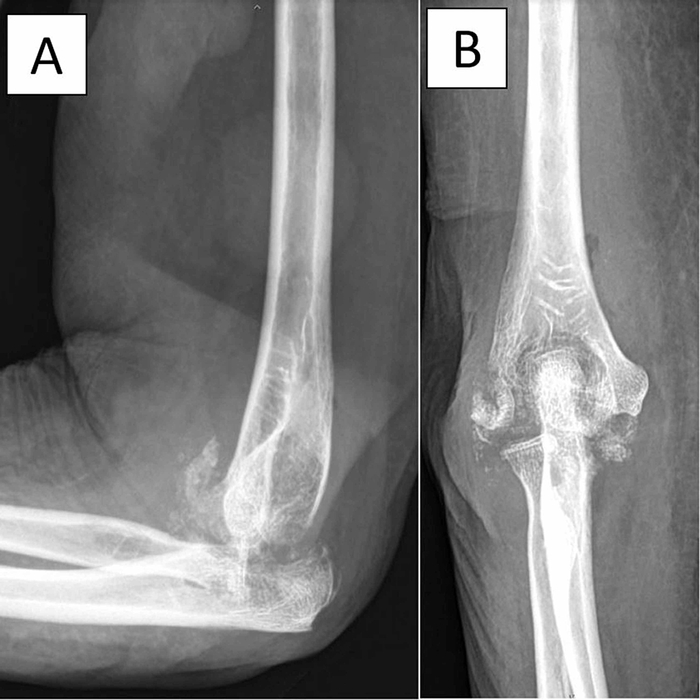

- Рентгенография - в основном для исключение перелома (если была травма), определения стадии деструкции сустава.

- МРТ - более точный метод диагностики, позволяет оценить состояние мягких тканей и костной ткани, увидеть отек кости, заподозрить остеомиелит.

Инфекционный артрит с остеомиелитом.